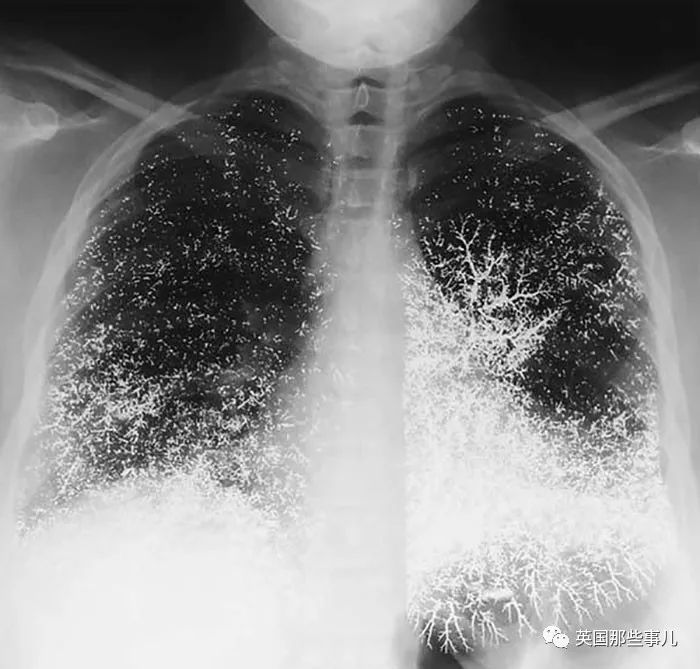

感染新冠肺炎五天後

靜脈注射水銀自殺未遂後,胸部變成了這樣....